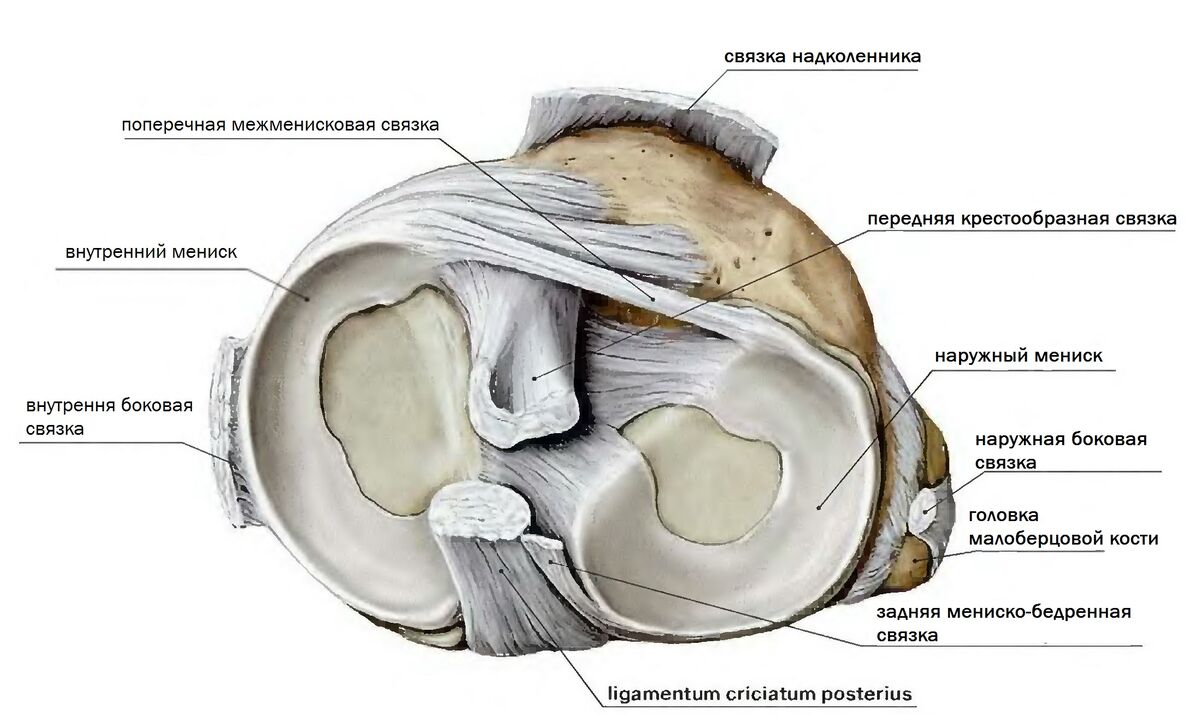

Анатомические изображения менисков и коленного сустава

Раздел: Иллюстрированные советы